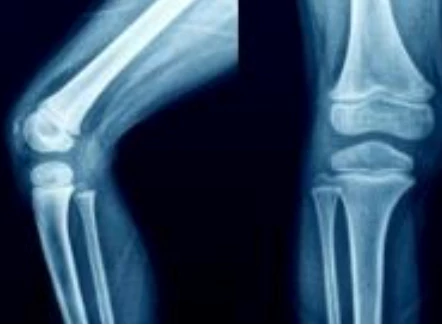

관절염은 뼈들이 만나는 지점인 관절에서 발생하는 질환으로, 이로 인해 관절 연골이 파괴되고 염증이 발생합니다. 이러한 관절은 인체의 움직임을 원활하게 하기 위해 상당히 중요한 구조로, 뼈들의 끝을 덮고 있는 연골은 마치 부드러운 쿠션처럼 작용합니다.

더불어, 관절을 둘러싼 활막이라 불리는 섬유질 막은 마찰을 최소화하고 관절 내부에서 움직임을 원활하게 합니다. 이 활막은 또한 활액을 생성하여 관절 내에서 뼈 사이의 마찰을 줄여주는 역할을 합니다.